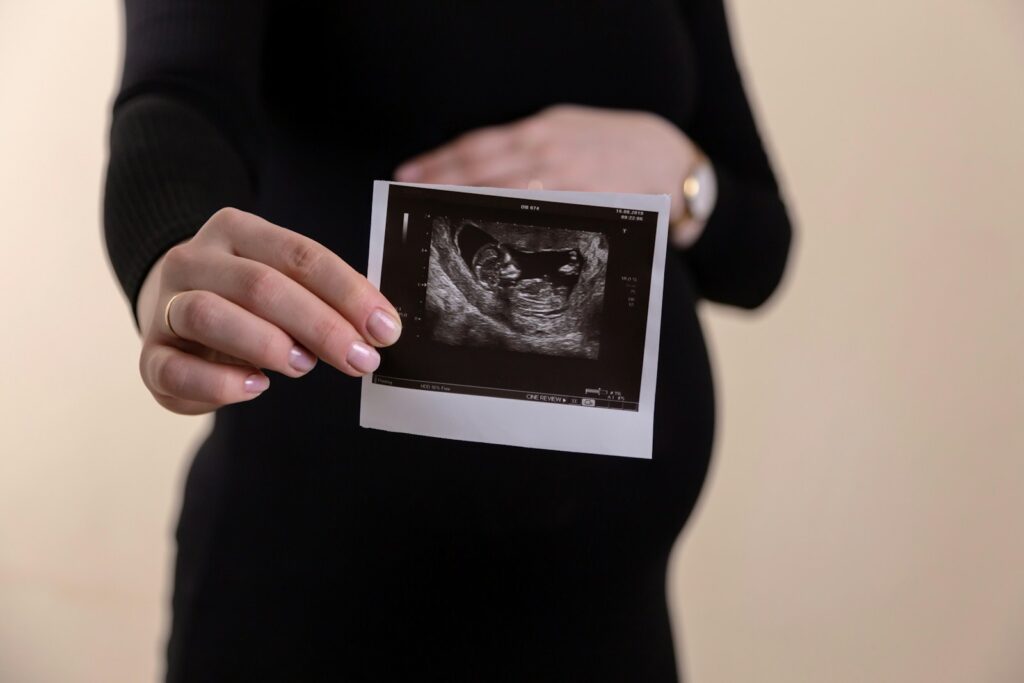

- USG połówkowe (18-22 tydzień) – najważniejsze badanie drugiego trymestru! Szczegółowa ocena anatomii dziecka. Można poznać płeć!

- USG połówkowe – najważniejsze badanie II trymestru! Szczegółowa ocena anatomii dziecka, można poznać płeć

USG połówkowe to szczegółowe badanie ultrasonograficzne wykonywane między 18. a 22. tygodniem ciąży (najczęściej w 20 tygodniu). Lekarz dokładnie ocenia anatomię płodu – sprawdza budowę mózgu, serca, kręgosłupa, twarzy, kończyn i wszystkich narządów wewnętrznych. To najważniejsze badanie, które pozwala wykryć ewentualne wady rozwojowe. Podczas tego USG można też poznać płeć dziecka!